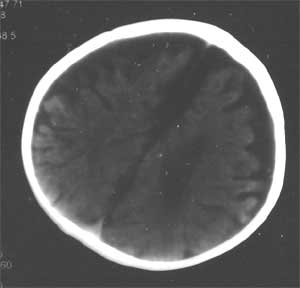

幕上幕下脑室、脑池、脑沟均见扩张积液,考虑脑发育不良。片子质量不好,前囟门似乎偏小,颅骨骨缝不知是否有闭合。9个月幼儿,头围应该不小于40厘米,请测量头围周径。应该没有胼胝体发育不良。至于“右侧基底节区缺血性改变”,片子质量差,看不清楚。

从ct片看1大脑纵裂增宽2侧脑室扩大3蛛网膜下腔增宽 应考虑1胼胝体发育不良,2脑发育不良或萎缩(两周前一般无临床意义应称蛛网膜下腔增宽或外周性脑积水)

不同意胼胝体发育不良的诊断,现在ct表现为脑沟、脑池增宽,双测额骨内板下方带状液体影,双测侧脑室略扩大,我认为应诊断为1、脑发育不全。2、外部性脑积水。情况应该很严重。

脑发育不良.半球间裂前后均宽.....不支持外部性脑积水,没有明确的胼胝体发育不良诊断依据.

片子比较暗。从这几张片子来看,大脑纵裂池似与侧脑室、三脑室交通,两侧额叶之间没有看到明显的脑白质交汇区(胼胝体膝部),如果是这样的话,应该考虑胼胝体发育不良。